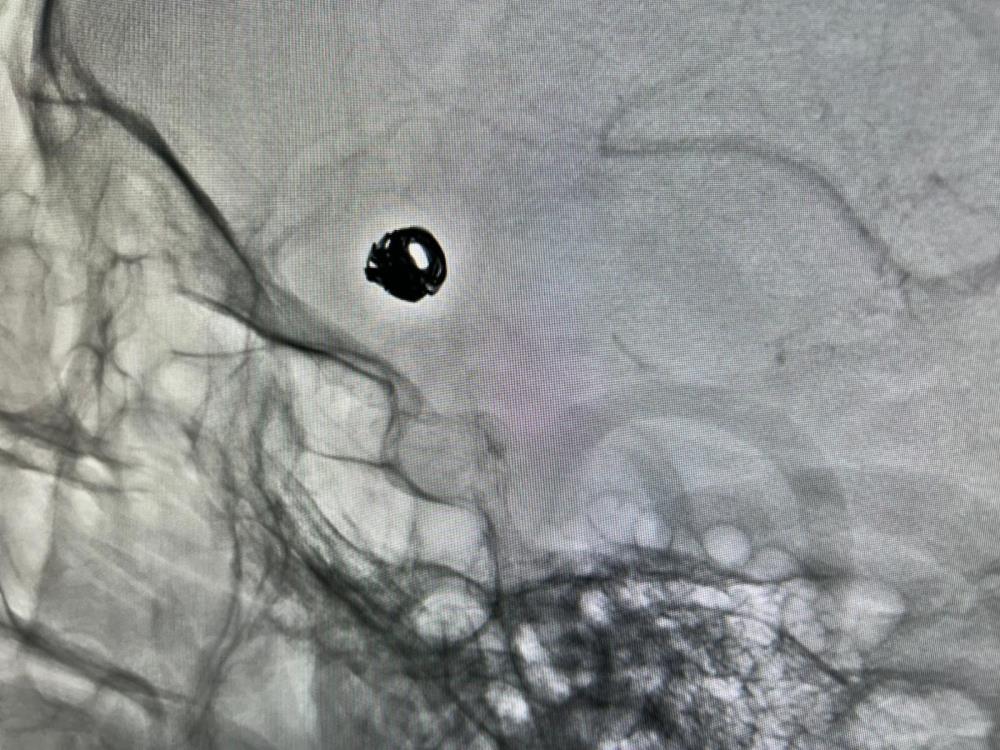

Konuya ilişkin açıklama yapan Hastane Başhekimi Doç. Dr. Remzi Sarıkaya, her türlü komplike hastanın merkezlerine sevk edildiğini belirtti. Doç. Dr. Sarıkaya, "Hastamızın dış merkezde yapılan tomografi incelemesinde beyin kanaması ve beyin damarlarında anevrizma tespit edildi. Bunun üzerine hasta 112 ambulansı ile Van Eğitim ve Araştırma Hastanesi'ne sevk edildi. Kasıktan girilerek beyin damarlarına ulaşıldı ve endovasküler (kapalı yöntem) tedaviye uygun olduğuna karar verildi. Yaklaşık 1,5 saat süren işlemde, anevrizmanın içine platin teller (coil) yerleştirildi. Bu sayede baloncuğun kanla dolması engellenerek yeniden kanama ihtimali ortadan kaldırıldı" dedi.

Hastaya ilk olarak anjiyo işlemi yapıldı. Kasıktan girilerek beyin damarlarına özel kateterlerle ulaşıldı ve anevrizmanın endovasküler (kapalı yöntem) tedaviye uygun olduğuna karar verildi. Yaklaşık 1,5 saat süren işlemde, anevrizmanın ağzına mikrokateterle ulaşılarak içine platin teller (coil) yerleştirildi. Bu yöntemle baloncuğun kanla dolması engellendi ve yeniden kanama ihtimali ortadan kaldırıldı" diye konuştu.